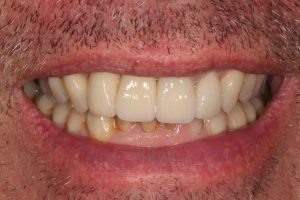

Upper Front Tooth Implant

Both upper front teeth were in a bad way, the upper left one had to be removed as was beyond repair, this was replaced with an implant and a temporary crown on the same day; the upper right front tooth was repaired with a crown. Photos show the result with the definitive crowns after 3 months of treatment.